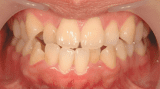

■症例1

Before

After